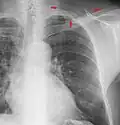

The margins of the supraclavicular fossa are often visible on chest X-ray